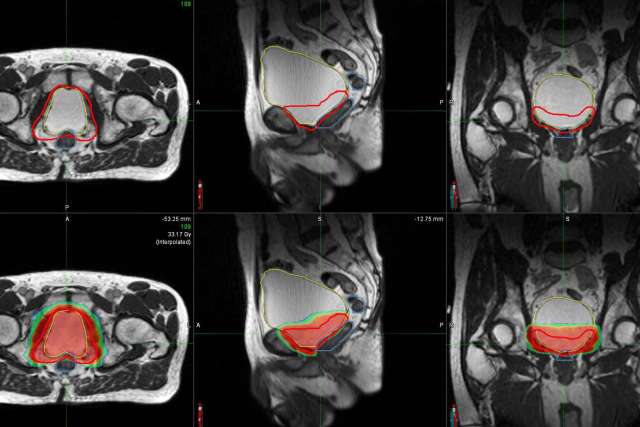

MRI scans showing cross-sectional views with outlined areas in red and green.

A new advance in radiation-therapy equipment is giving physicians the ability to better visualize tumors and internal anatomy, allowing more accurate delivery of necessary treatments.

The equipment, called the MRIdian LINAC, is an improvement over older technologies, because it uses a built-in MRI to guide radiation treatment in real time, explains UCLA Health radiation oncologist Amar Kishan, MD.

“This makes a critical difference,” says Dr. Kishan. “MRIs have a much better spatial resolution than a CT scan,” which has been the traditional method to locate and map out areas that need to be treated but has limitations because it does not always provide the clearest picture of internal anatomy, particularly in the abdomen and pelvis.

Because MRIdian can see and track soft tissue and tumors in real time, it “allows physicians to adjust radiation treatment to more accurately deliver this therapy at the right dosage and to exactly the right area,” Dr. Kishan says. This form of external beam radiation therapy allows radiation oncologists to provide treatment while reducing the exposure of healthy tissues.

Because of MRIdian’s improved effectiveness in accounting for daily changes in anatomy, Dr. Kishan and his research team are able to safely deliver higher doses of radiation to patients. Dr. Kishan explains that after prostate cancer surgery, for example, the treatment is delivered in the space between the bladder and the rectum. These two organs change in size. This makes the MRI-guided treatment with better resolution an improved option for more precise prostate cancer treatment.